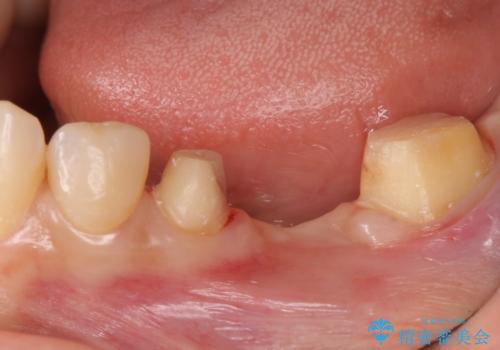

- 左下の銀歯の状態が悪く抜歯してブリッジにした患者様です。

抜歯してからブリッジの仮歯をすぐ入れるため、歯がない期間はほとんどありません。